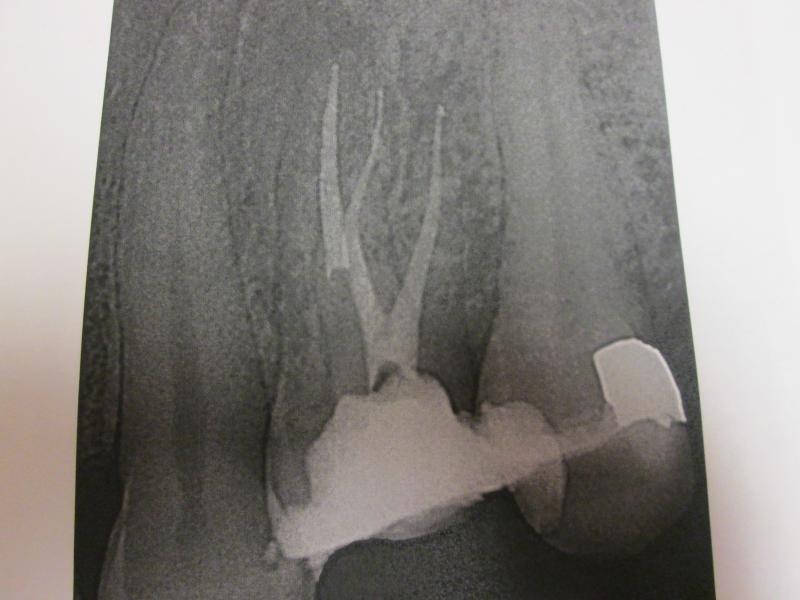

"DR. JET'S MISSION IS TO PERFORM  ROOT CANALS FOR A REDUCED FEE USING THE LATEST TECHNOLOGY  AND TECHNIQUES TO SERVICE THE MANY PEOPLE WHO ARE UNINSURED OR UNDER-INSURED GIVING EVERYONE AN OPPORTUNITY TO SAVE THEIR TOOTH!"

**PLEASE BE AWARE THAT  A ROOT CANAL IS AN ATTEMPT TO SAVE YOUR ALREADY DAMAGED TOOTH.  THERE IS NO GUARANTEE THAT ANY TOOTH CAN BE SAVED BUT DR JET WILL DO HIS BEST TO HELP YOU. THE OTHER OPTION IS TO EXTRACT YOUR TOOTH